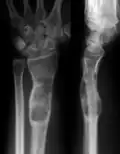

| X-ray image showing enchondromas localized in the lower part of the radius of a 7-year-old girl with Ollier disease. | |

Abnormal bone growth such as shortening or thickening and deformity may be observed in patients of Ollier disease. These bone lesions are visible at birth using radiography but are usually not screened or examined for until clinical manifestations present during early childhood. However, some patients may exhibit no signs of any symptoms.[1] One study found thirteen to be the mean age of diagnosis in patients with Ollier disease. In an X-ray, there would normally be the presence of several homogeneous lesions of an oval or elongated shape with bone edges that are slightly thickened.[3] With age, these lesions may calcify and appear as diffusely minute spots or stippled. Fan-like septations or streaks would be indicative of the presence of several enchondromas. Early detection and consistent and repeated monitoring is important in order to prevent and treat any potential bone neoplasms.

X-ray showing enchondromas localized in the lower part of the radius of a 37-year-old patient affected with Ollier disease -